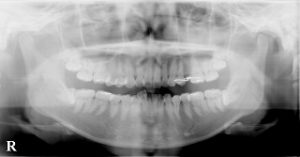

口腔外科(インプラント)、歯科・矯正歯科(歯列矯正)、 アメリカ式の根管治療(Endodontics,Rootcanal treatment),を中心に

虫歯治療、歯周病治療(歯槽膿漏)を総合的に治療し、お口の健康と若さを維持する治療を行っております。